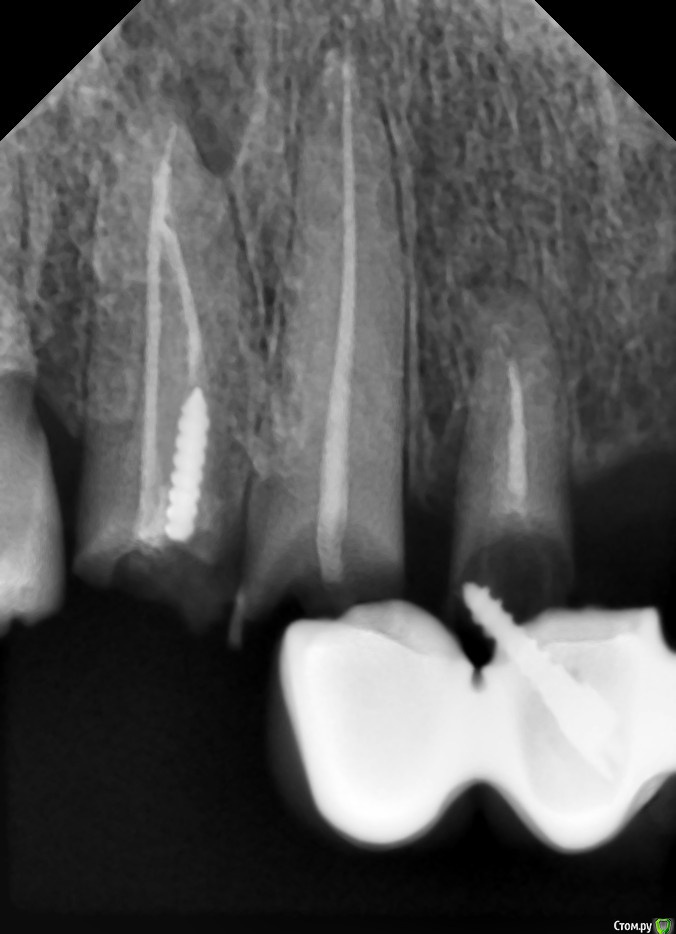

Витторио Орлионе Опубликовано 12 декабря, 2016 Поделиться Опубликовано 12 декабря, 2016 Здравствуйте, уважаемые форумчане. Поделитесь пожалуйста своим мнением и опытом вот по такому случаю: пациентка 40 лет обратилась с жалобами на подвижность мостовидного протеза и хочет реабилитации. Импланты позволить себе не может и очень хочет несъёмную конструкцию. Пожалуй самый главный вопрос: что целесообразней: перелечить те из опорных зубов, которые ещё можно сохранить и покрыть их коронками или удалить все корешки и восстановить их уже в съёмном протезе? Возможно ли использовать эти корни для лучшей фиксации протеза во рту и как? Ссылка на комментарий

Витторио Орлионе Опубликовано 13 декабря, 2016 Автор Поделиться Опубликовано 13 декабря, 2016 Сегодня мостик сняли и вот что под ним было. А что касается верхних моляров, то 2.8 весь в кариесе, 2.7 уже с 1 степенью подвижности, и выдвинулись они там мм на 3 что в 1м, что во 2м сегменте.пожалуй стоит задуматься о пспп. Ссылка на комментарий

StomV Опубликовано 14 декабря, 2016 Поделиться Опубликовано 14 декабря, 2016 Сегодня мостик сняли и вот что под ним было. А что касается верхних моляров, то 2.8 весь в кариесе, 2.7 уже с 1 степенью подвижности, и выдвинулись они там мм на 3 что в 1м, что во 2м сегменте.пожалуй стоит задуматься о пспп. Вот вопрос о сохранении отпал сам собой. Ссылка на комментарий